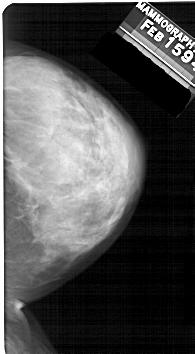

A_1326_1.LEFT_MLO

LEFT_MLO LINES 5491 PIXELS_PER_LINE 3166 BITS_PER_PIXEL 12 RESOLUTION 43.5 OVERLAY